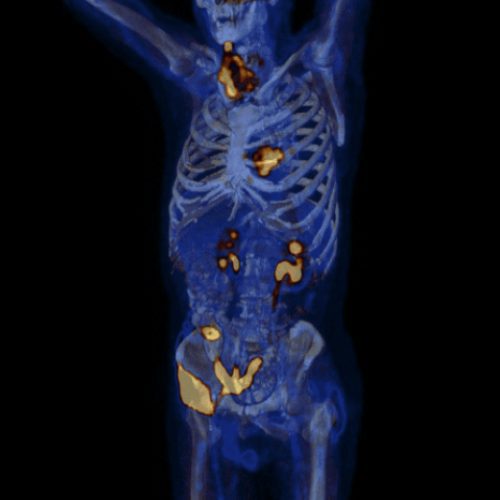

Ejemplos de imágenes del PET-CT mostrando ubicaciones de los órganos y FDG acumulado.

La tomografía PET detecta en dónde se ha acumulado el FDG en el cuerpo. Por lo tanto, el estudio detecta la ubicación del cáncer metastásico.

• El cáncer metastásico está formado de células hipermetabólicas.

• Las células hipermetabólicas usan más azúcar (glucosa) que las células normales.

• La glucosa radioactiva (FDG) es inyectada de forma intravenosa.

• Durante el periodo de relajación, el FDG se acumula en las células hipermetabólicas.

• La mesa mueve al paciente a través del escáner TC (5 min).

• La mesa mueve al paciente a través del detector de FDG (15 min).